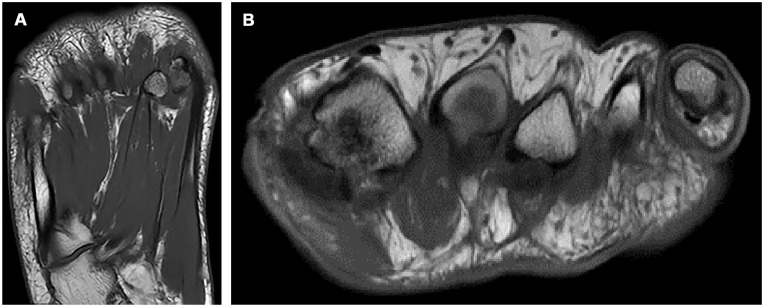

Concurrent Heuter's and Morton's Neuromata Following Hallux Valgus Surgery: A Rare Case and Review of Terminology.

Visual AbstractThis is a visual representation of the abstract.